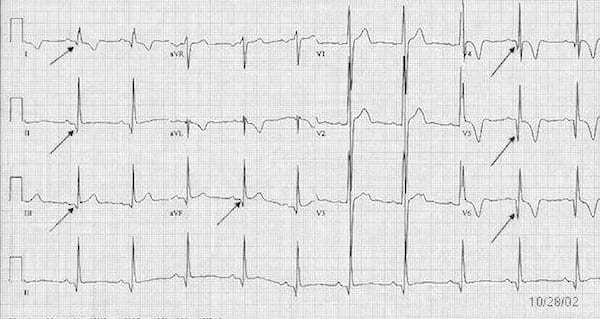

What’s the Rhythm?

Sudden Cardiac Death